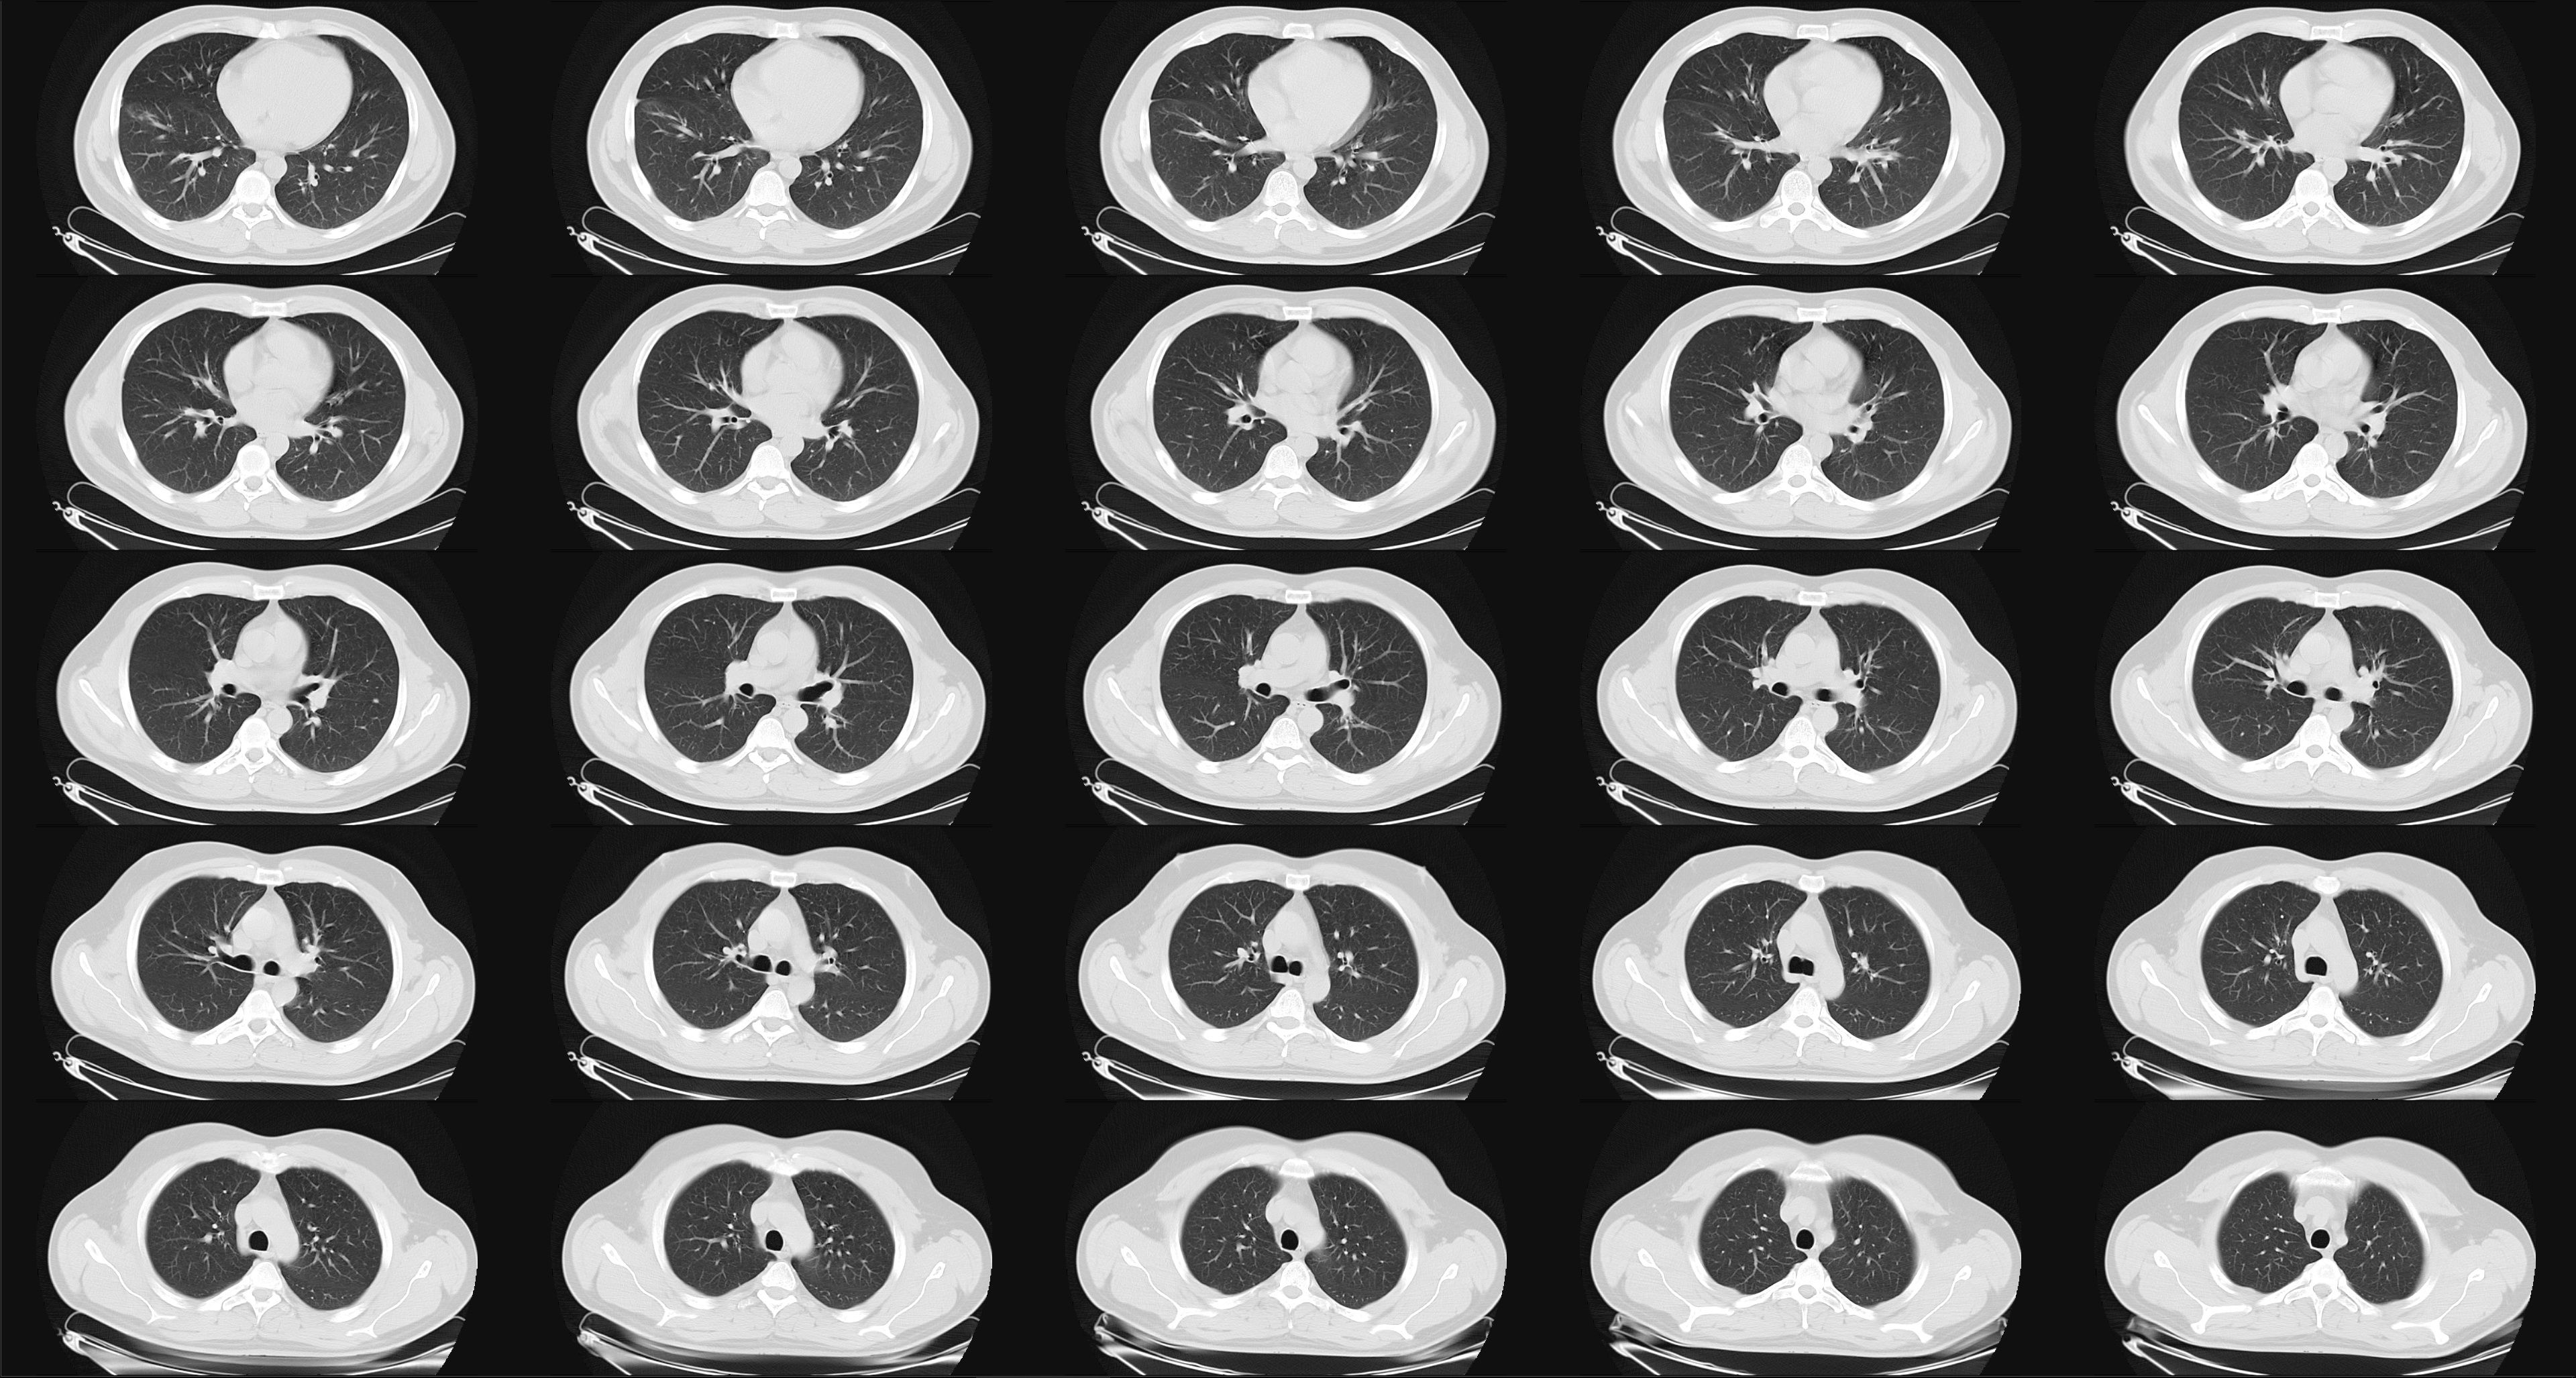

Computed tomography (CT) abnormalities are reported among a substantial proportion of patients after hospitalization with COVID-19.

Screening for COVID-19 exposure, particularly for patients with cancer on active treatment, has become a priority during the pandemic.